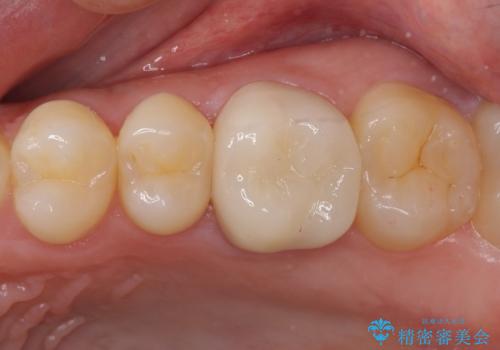

折角なのできれいに仕上げたいとのことで、オーダーメイドタイプのクラウンを選択されました。色調を周りのご自身の歯と合わせることができるため、自然な仕上がりをご希望の方におすすめです。